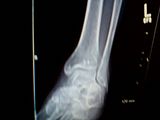

heres a closeup. best i could get off this camera lol these films WERE done 8/19 . 14 hours after fall and i dont see it fracture of left ankle/lower leg and an aha moment.. anyhoo the closeup: